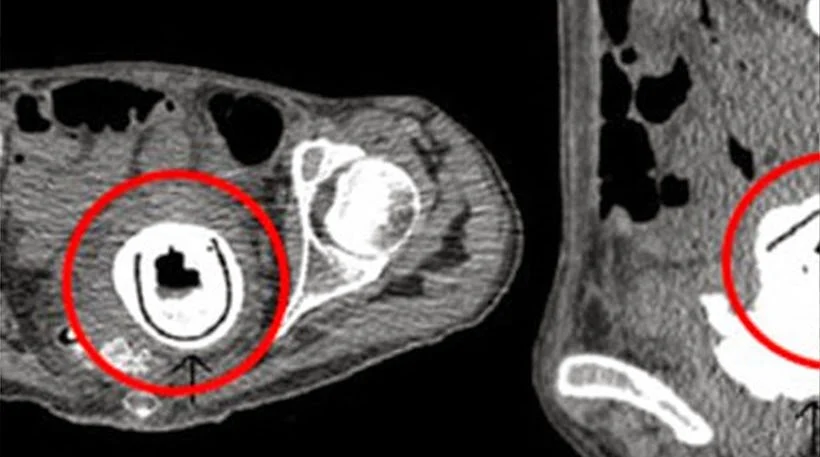

Το sex toy, μήκους 12 εκατοστών «αποκαλύφθηκε» όταν οι γιατροί υπέβαλαν τη γυναίκα σε μια σειρά από ακτινογραφίες

Το ερωτικό βοήθημα, μήκους 12 εκατοστών «αποκαλύφθηκε» από τις ακτινογραφίες στις οποίες

υπέβαλαν οι γιατροί τη γυναίκα, όταν εκείνη έσπευσε στο νοσοκομείο, λέγοντας ότι αισθανόταν κουρασμένη, ότι υπέφερε από υπνηλία, από συχνές ουρολοιμώξεις και πως έχανε συνεχώς βάρος.